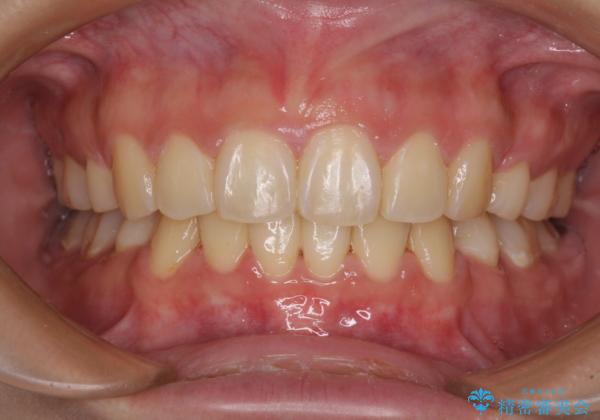

治療後には口が閉じやすくなり、患者様には大変満足していただきました。